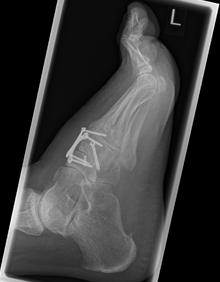

2.-Postoperatives Bild Februar 2017

4.- 06/2017 nach Rearthrodese

Bei einer Verlaufskontrolle im Juli 2017 ergab sich bei der Röntgenuntersuchung eine Fehllage einer Plattenschraube, die damit das TMT 2 überbrückte.

5.- 07/2017 Schraubenfehllage : Schraube erreicht Basis MT2 und überbrückt TMT 2